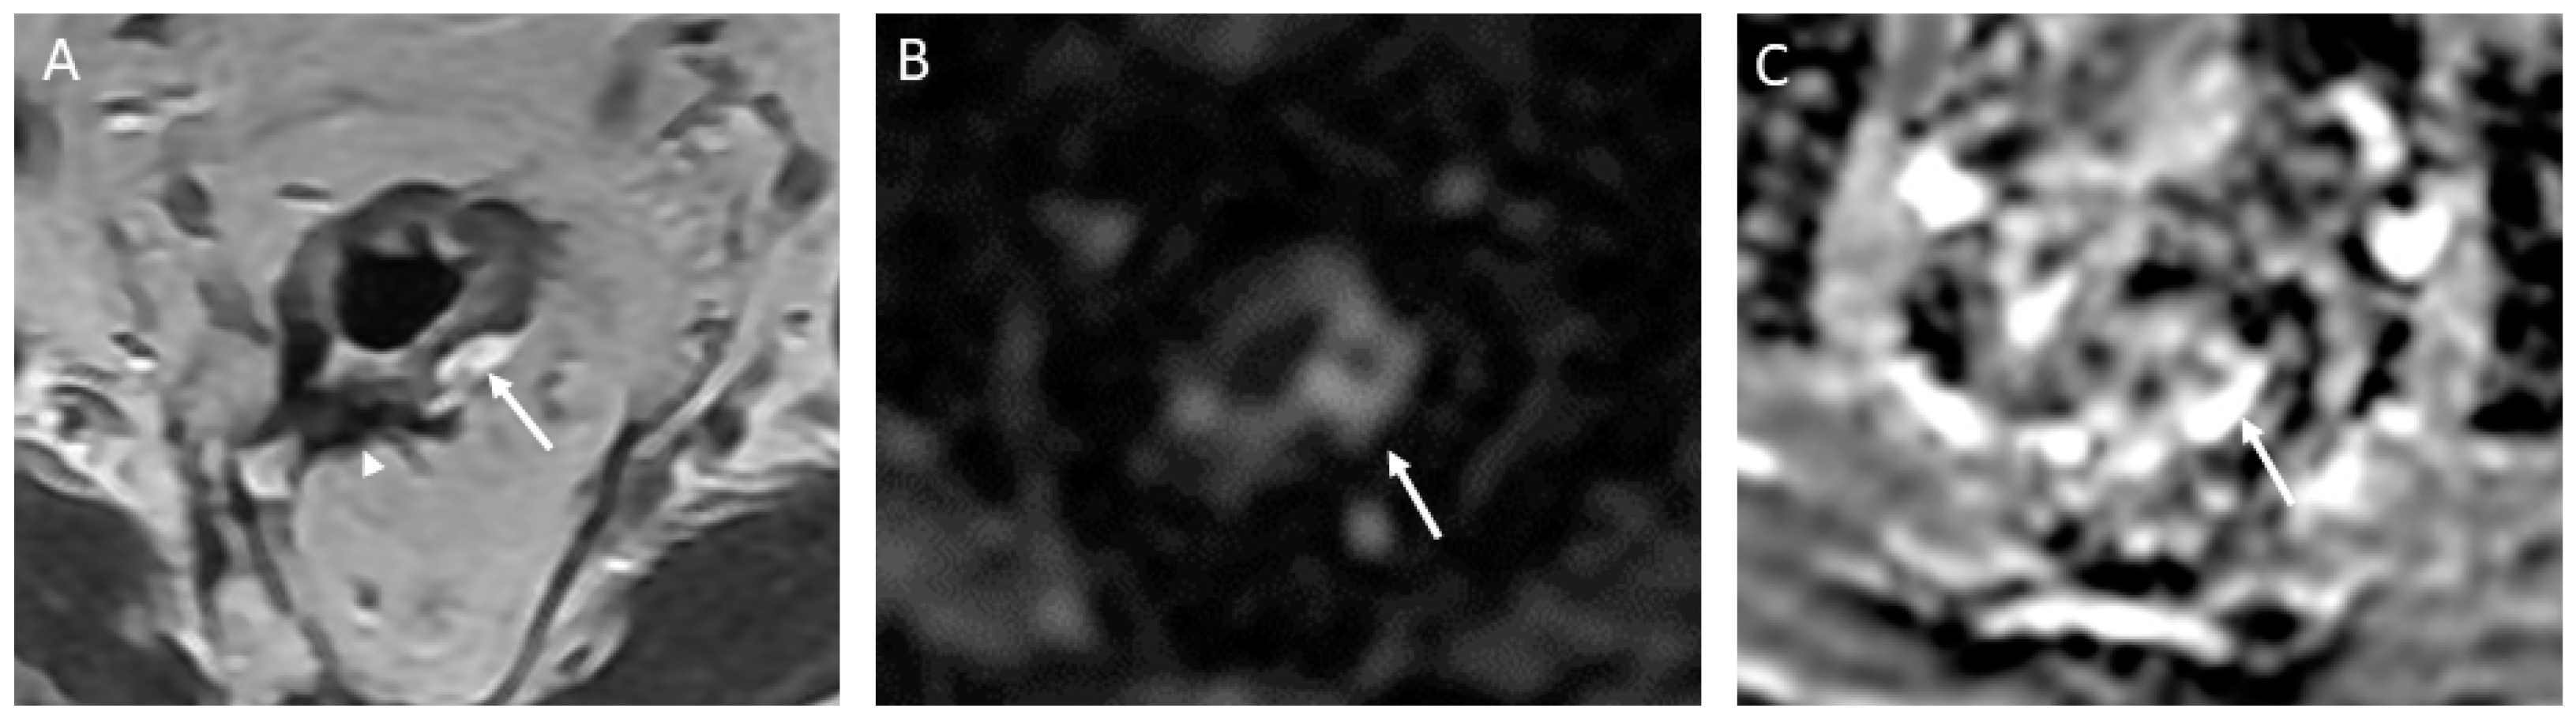

- iCR characterizes the scenario where tumor volume experiences a reduction, but discernible residual tumor persists. This response type manifests through persistent diffusion restriction and the persistence of T2 intermediate signal within the tumor bed (Figure 4).

Figure 4.

Incomplete response in a 60-year-old man with low/middle rectal adenocarcinoma. (A) Baseline axial T2-weighted MR image shows an intermediate-signal-intensity, near-circumferential low rectal tumor (dotted line). (B) Axial T2-weighted MR image after the completion of neoadjuvant chemoradiotherapy shows persistent intermediate signal intensity (arrow) representing incomplete response and residual tumor. (C) Axial diffusion-weighted image shows high signal intensity (arrowhead). (D) The residual malignancy was identified at endoscopy. The patient underwent total mesorectal excision.